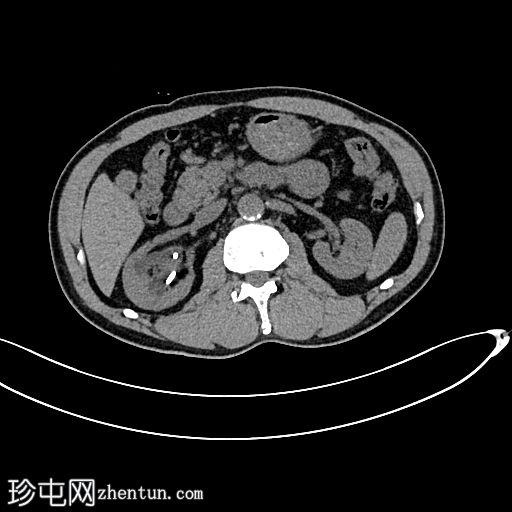

CT扫描

轴位

平扫

可见中度右肾积水和输尿管积水。右肾双极长10.6厘米。可见输尿管支架,近端位于肾上极肾盏,远端位于膀胱内。肾下极可见肾结石。肾下极可见肾皮质囊肿,囊壁薄,内含钙化。肾上极可见肾实质钙化。在支架旁远端输尿管(S1至S2椎体水平)可见少量输尿管结石。

左肾双极长9.2厘米。肾上极和肾下极可见微小结石。未见输尿管结石。无肾积水或输尿管积水。肾上极可见肾皮质囊肿。

膀胱轮廓正常。未见膀胱结石。